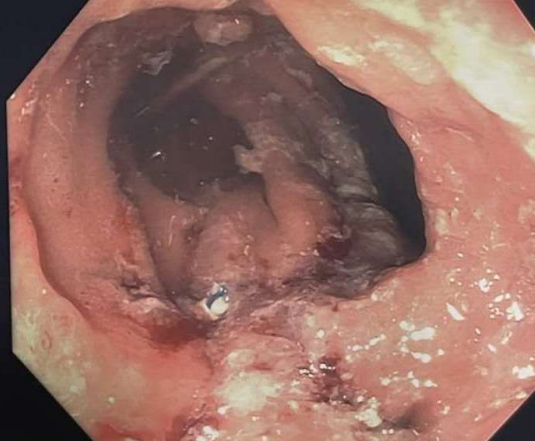

75-year-old man with chronic kidney disease on hemodialysis, atrial fibrillation and history of Roux en-Y gastric bypass was admitted with cholangitis from bile duct stones. His blood culture grew Escherichia coli, klebsiella pneumoniae and Enterococcus faecium. EUS directed trans-gastric ERCP (EDGE) was planned. EGD showed severely inflamed gastric pouch with a large marginal ulcer (Fig A). The patient was too unstable for Lap assisted ERCP. The patient underwent successful single session EDGE with placement of a 20 mm x 10 mm Axios stent (Boston Scientific Corp, Marlborough, Mass, USA) through an area that did not involve the large ulcer (Fig B). Plastic stent was placed initially and two weeks later, the stones were successfully removed using cholangioscope and EHL. Four weeks later EGD showed gastro gastric fistula (Fig C) and LAMS has been spontaneously expelled. The ulcer has completely healed. The fistula was closed after APC ablation by endoscopic suturing (using Apollo Endo stitch) (Fig D). Patient was discharged in stable condition and follow up one month later the patient was doing well.

Figure A, B, C, D